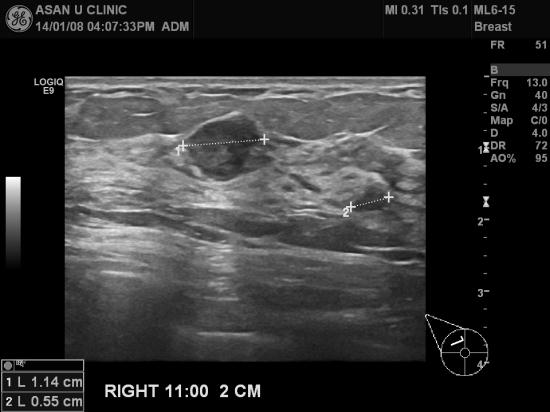

아산유외과 개원 후 56번째 유방암 진단.

건강검진상 이상소견으로 의뢰된 41세 여성분입니다.

우측유방 상외측에 세개의 혹이 각각의 조직검사상

침윤성 유관암, 비정형 유관 증식증으로 나와

유방의 MRI로 잔여부위의 잔존암 가능성을 검사하고 계십니다.

다행이도 가장 큰 혹이 1.1cm으로 크지 않아

초기로 예상하고 있습니다.

빠른 쾌유를 기도합니다.